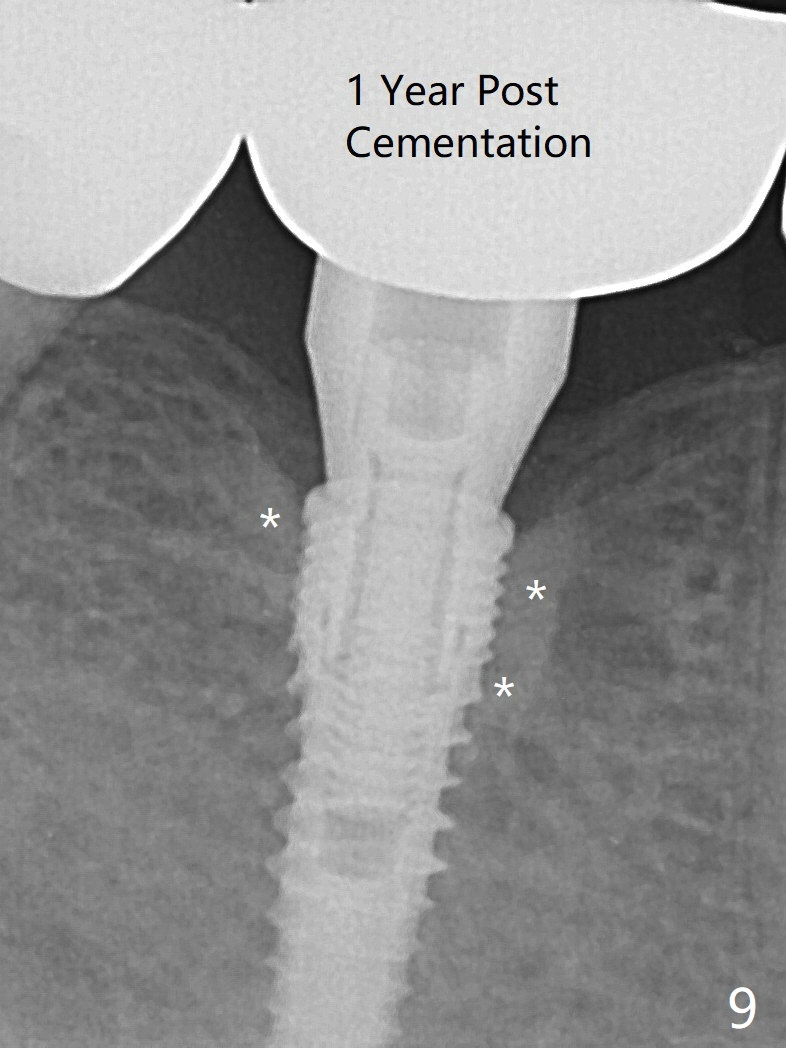

When a 3.8x12 mm SM implant is placed with 40 Ncm, there is 1-2 mm cortical bone buccolingually (primary stability, Fig.4,5). The thick cortices do not seem to be easy to be bent, i.e., expanded. There appears dense bone formation 3 months postop (Fig.8 *). One year post cementation, the crown at #31 needs recementation (Fig.9); the bone density next to the coronal implant increases (*).